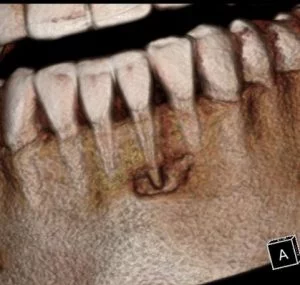

A CBCT was taken after a negative cold test indicated a necrotic tooth. When the CBCT was taken, we could clearly see that the abscess had completely perforated the labial bone at the apex of #24 and was close to doing so on #25.

As we investigated more deeply, we identified another critical piece of information that would affect our treatment plan: a second canal on #24.

Had I initiated treatment on this particular tooth and kept my access very conservative, there’s a chance I would have missed the other canal. Furthermore, had I started the treatment and then found the second canal after access into the chamber, I would have had to spend time determining the anatomy of both canals. For example, I would have had to determine if they had separate apicies.